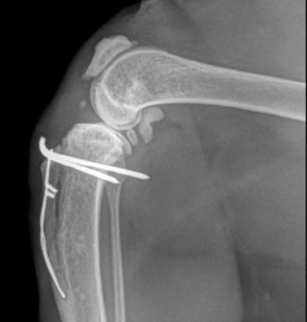

고양이 무릎 관절낭 내부에 양성 골종양이 생긴 증례이다.

결론적으로 수술 후 행복하게 잘 살았답니다~ 가 끝이다.